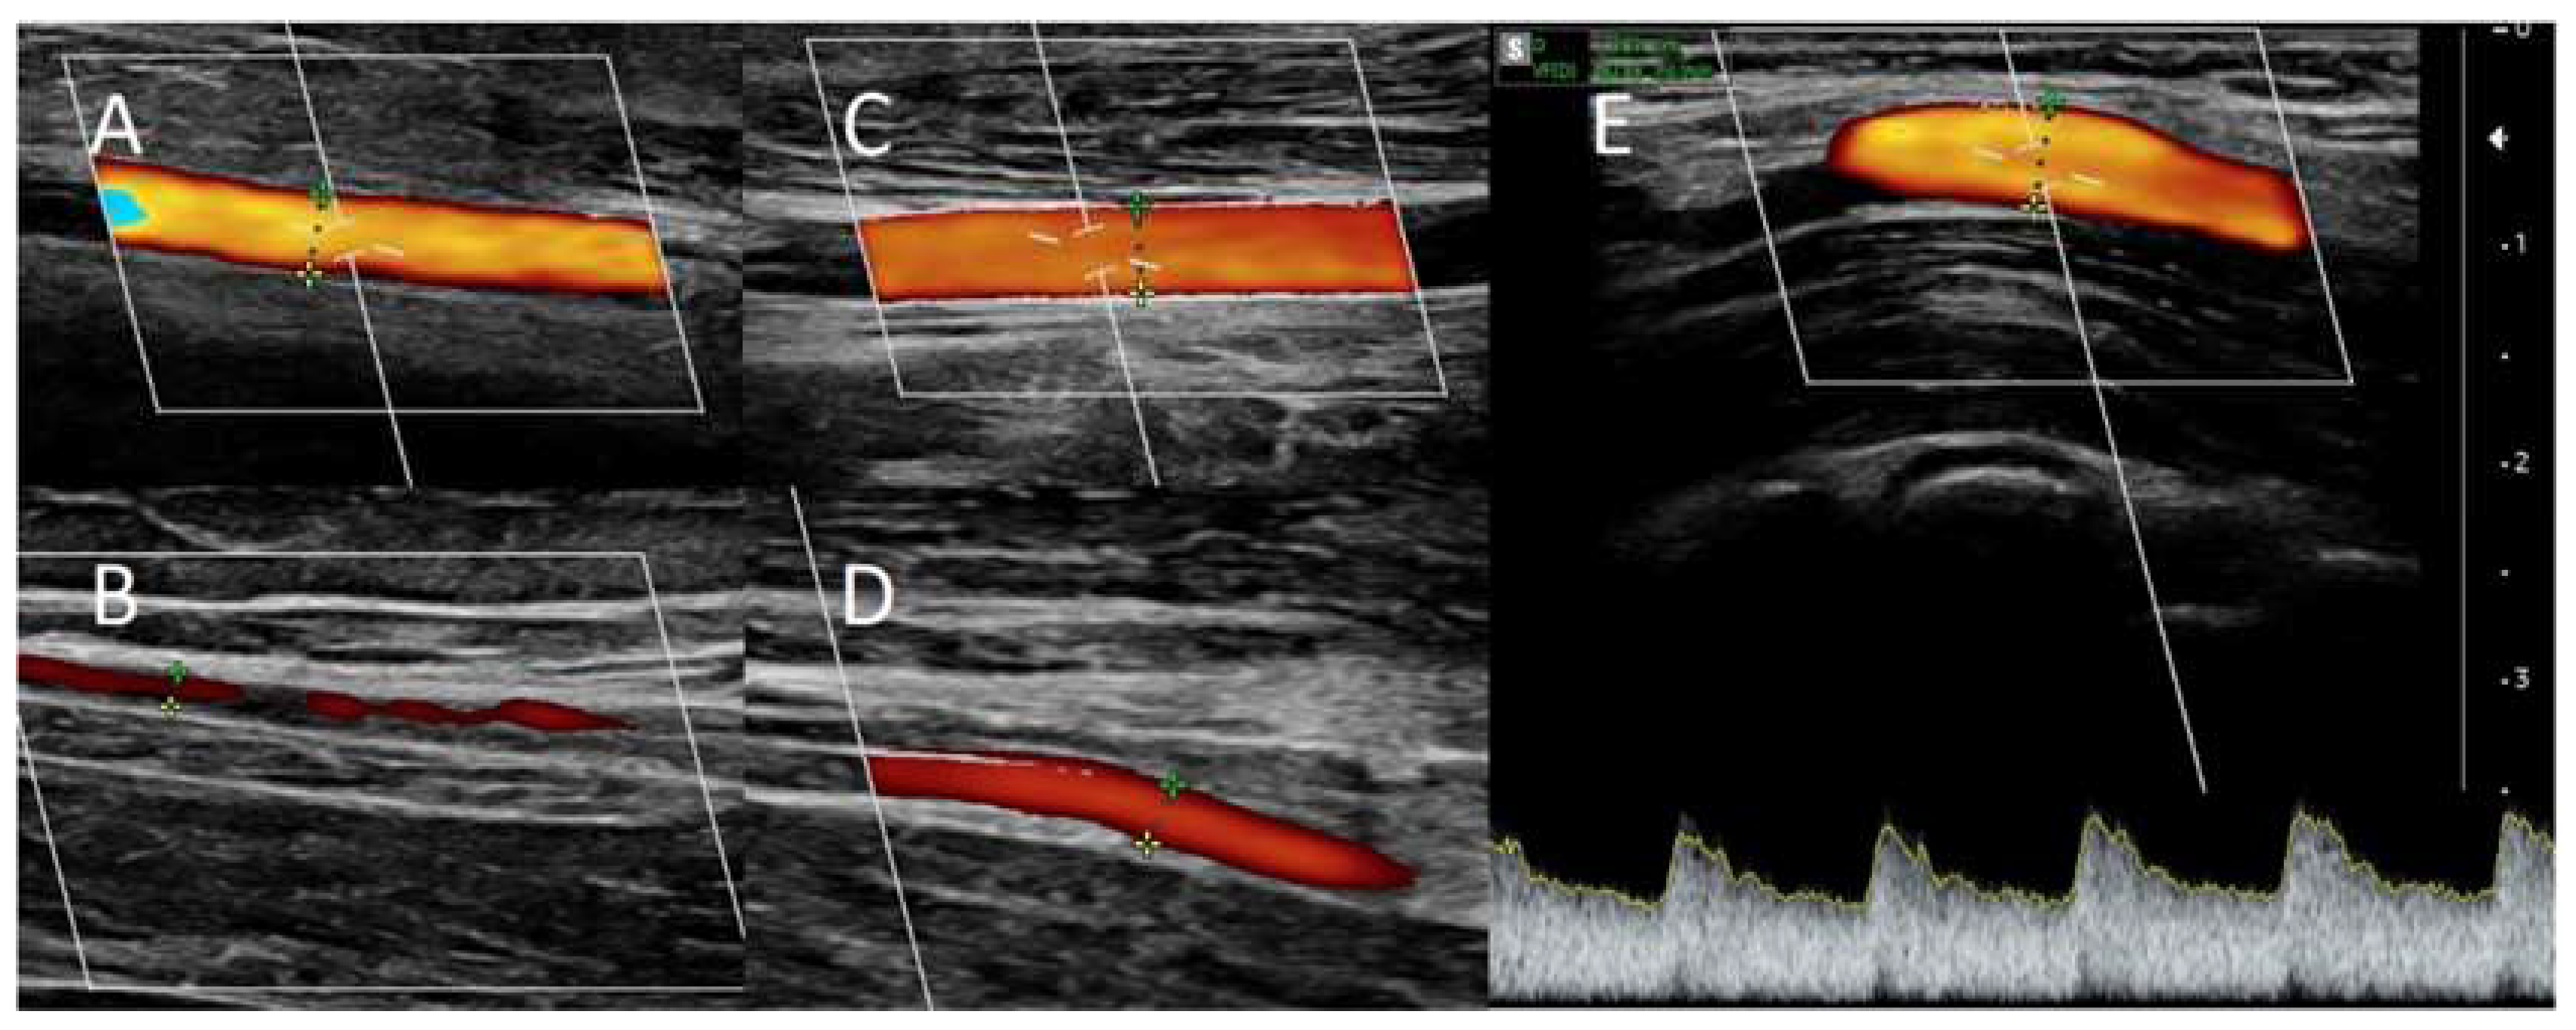

Local anesthesia consisting of 1% lignocaine solution was used during the procedure. An oblique incision was made in the distal part of the forearm, approximately 2 to 3 cm proximal to the primary fistula (Figure 2B). The appropriate vessel fragments were dissected. Over the ligature, the radial artery was severed, and the blood supply was verified by momentarily releasing the clamp. The perceived blood flow was satisfactory. The cephalic vein was then clamped both distally and proximally and finally, and it was subsequently incised longitudinally. Both vessels were sutured with a continuous suture, i.e., the end of the artery was anastomosed with the side of the vein using an insoluble polypropylene vascular suture of 6-0 (Figure 2B). During the procedure, the operator used a magnifying glass with 2.5 times magnification. We present the patients in whom option I of anastomosis (Figure 1) was performed; however, option II was carried out in two additional cases. The vein filled with blood when the clamps were removed, and a typical murmur was noticed (Figure 2B). The wound was closed using skin sutures. Ultrasound examination confirmed that the fistula was patent the day following the procedure. UA and RA diameter was 4 mm and 2 mm, respectively (Figure 3C,D). The blood flow rate through the UA was 193 ml/min (Figure 3C), while the brachial blood flow rate was 482 ml/min (Figure 3E). The patient was discharged with a fistula that was functional. At the 3-week postoperative follow-up appointment, the fistula remained patent, and the first successful cannulation was performed 4 weeks after surgery (Figure 1C).

Figure 3. Doppler ultrasound: A) of the ulnar artery before RADAR intervention, B) of the radial artery before RADAR, C) of the ulnar artery after RADAR, D) of the radial artery after RADAR., E) Blood flow in brachial artery after RADAR intervention.